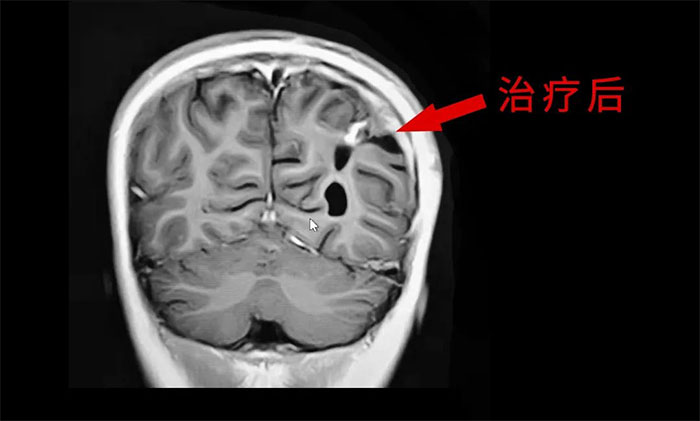

于耀宇主任特别指出,随着脑血管介入技术快速发展,脑胶质瘤术后超选介入化疗联合同步放疗的效用正逐渐为大家所认识。超选介入化疗,是利用微导管技术直接将药物通过供血动脉,灌注到颅内肿瘤组织区域,避免了传统口服或静脉注射药物,要经过全身代谢后才能到达肿瘤区域。可减轻全身毒性反应,延长化疗药在肿瘤内的滞留时间,更好地杀伤肿瘤细胞。

最后,于耀宇主任表示,胶质瘤固然凶险,但我们应当正确认识疾病,不盲目悲观,更不应轻易放弃治疗。随着医疗技术水平和治疗手段的不断提高,胶质瘤患者在接受规范的治疗后,延长生存期已成为可能,大可不必“谈瘤色变”。